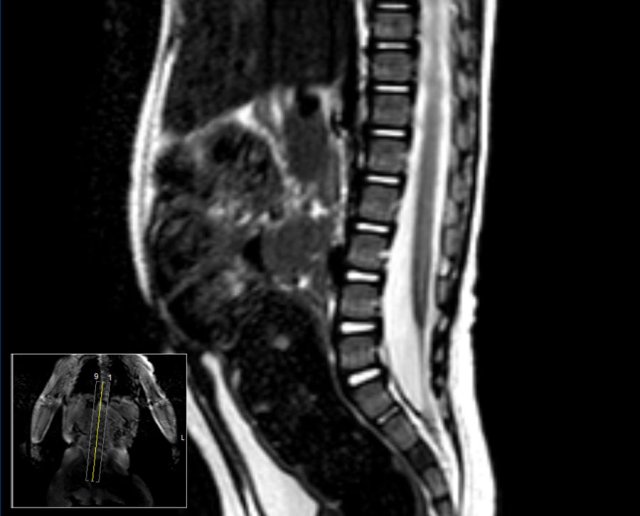

Here images of a newborn, who had several antenatal anomalies.

There was a lateral rocker bottom feet deformity, lumbar kyphoscoliosis and swelling on the lower back.

The spinal US and MR show a longitudinal split of the spinal cord at the thoracolumbar level.

The bifid cord is asymmetric in volume.

Additional plain films of the lumbar spine and pelvis showed thoracic and lumbar hemivertebrae.

There was also a dislocated left hip.